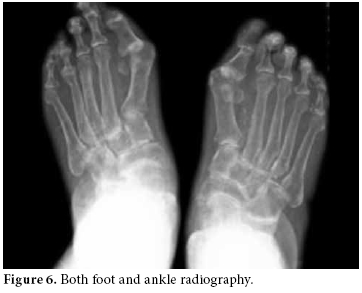

The RA disease activity score (DAS) was calculated as 6.14. Predominant findings in hand X-rays were symmetric joint erosions in carpal bones along with ankylosis leading to contracture, joint space narrowing, cystic changes, and periarticular osteoporosis (figure 5).

In foot-ankle X-rays, periarticular osteoporosis, hallux valgus, and joint space narrowing had progressed to the ankylosis of tarsal bones (figure 6).